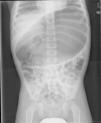

Presentamos 2 casos de vólvulo gástrico crónico. El primero, un niño de 5 años sin enfermedades previas que acudió a urgencias para segunda opinión por episodios de distensión abdominal intermitentes de un mes de evolución. La exploración era normal salvo un abdomen discretamente globuloso y timpánico. Se realizó ambulatoriamente tránsito baritado que fue normal. Escasas horas después presentó episodio de distensión abdominal y en la radiografía de abdomen se observaba imagen compatible con vólvulo gástrico (fig. 1). Ante los hallazgos se introduce sonda nasogástrica y se realizó intervención quirúrgica laparoscópica en la que se objetivaba un ligamento gastrocólico laxo que permitía volvulación gástrica completa organoaxial. Se realizó gastrofrenopexia (fijación del estómago al diafragma) y gastropexia anterior (fijación a pared abdominal anterior). El curso del paciente fue favorable.

El diagnóstico suele realizarse mediante la radiografía de abdomen y un tránsito esófago-gastro-duodenal3 aunque a veces estas pueden ser normales4. Por ello, se deberá recurrir a otras técnicas de imagen como la TAC si la sospecha clínica es alta y las pruebas anteriormente mencionadas son normales. Según el eje sobre el que se produzca el giro del estómago, el vólvulo será órgano-axial (54% de los agudos y 85% de los crónicos)1, mesentérico-axial (41% de los agudos y 10% de los crónicos)1 o mixto5. Los hallazgos incluirían distensión masiva, posición anómala gástrica, dos imágenes de niveles hidroaéreos, «pico de ave» en la unión esofagogástrica, etc. En el órgano-axial el estómago tiene plano horizontal con la curvatura mayor superior a la menor. En el mesentérico-axial la unión antroduodenal está encima de la gastroesofágica y el plano gástrico es vertical, con forma esférica.